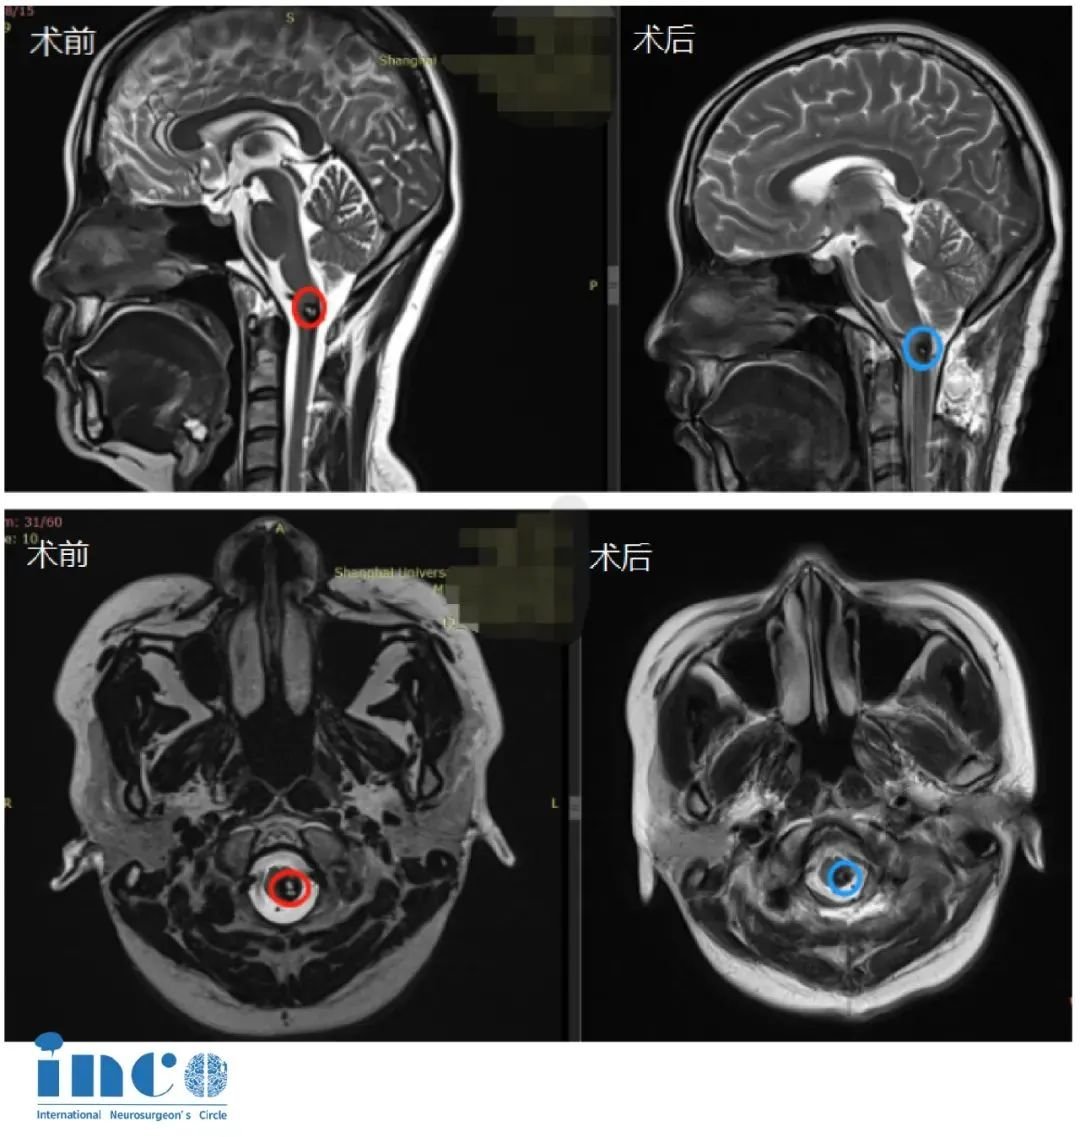

術(shù)中,巴教授憑借豐富經(jīng)驗,在助手密切配合下,精準(zhǔn)避開密集的血管神經(jīng),清晰顯露并成功全切了腦干部位的海綿狀血管瘤。手術(shù)過程順利,患者生命體征平穩(wěn)。

影像

術(shù)后第二周:王女士便順利出院,迅速回歸正常生活與工作。出院時,術(shù)前癥狀已顯著改善。術(shù)后影像學(xué)檢查證實腫瘤完全切除。

術(shù)后兩年隨訪:巴教授評估其最新MRI影像后確認(rèn):“考慮到既往出血史,目前復(fù)查核磁顯示病情非常穩(wěn)定”,明確表明血管瘤全切后兩年無復(fù)發(fā)。鑒于王女士狀態(tài)良好,巴教授建議后續(xù)復(fù)查可安排在兩年后進(jìn)行。